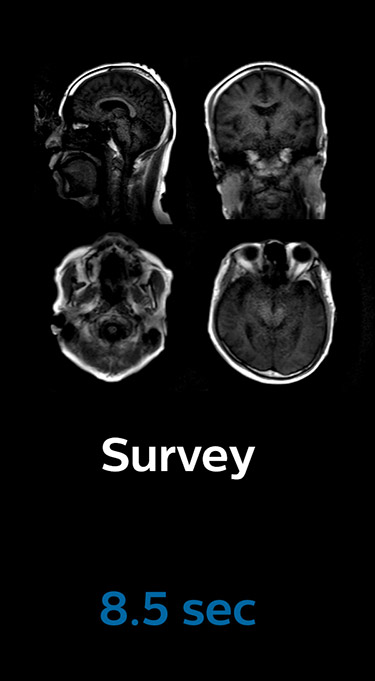

Scanning time reduction in brain MRI with Compressed SENSE

Fast MRI of brain

With Compressed SENSE, the scan time for the routine brain examination at KNC was reduced from 15:48 to 10:19 minutes, which corresponds to 35% reduction.

Ingenia 3.0T CX

Scan time 15:48 min.

Brain with Compressed SENSE

Ingenia 3.0T CX

Scan time 10:19 min.